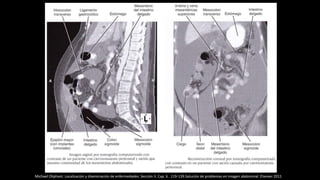

Michael Oliphant. Localización y diseminación de enfermedades. Sección II. Cap. 6 . 119-139.Solución de problemas en imagen abdominal. Elseiver 2011

TC abdominopélvico tras la administración de contraste endovenoso. Liquido libre

perihepático y presencia de burbujas aéreas extraluminales en relación con

neumoperitoneo. Neumoperitoneo contenido secundario a perforación duodenal

Neumoperitoneo-TC abdominal